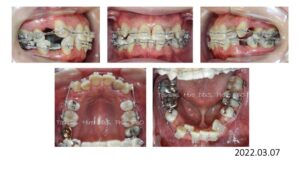

次の症例は叢生です。

50歳の女性です。娘さんがうちで治療した数年後、自分も歯並びを治したいと希望され、治療を開始しました。

上下両側4番抜歯後、上下顎にブラケットを付け、

スペースクローズが終わり、細部の仕上げを行い、

治療期間 2年 7か月で動的治療を終了しました。

人前で笑えるようになりました、と、とても喜んで頂く事が出来ました。